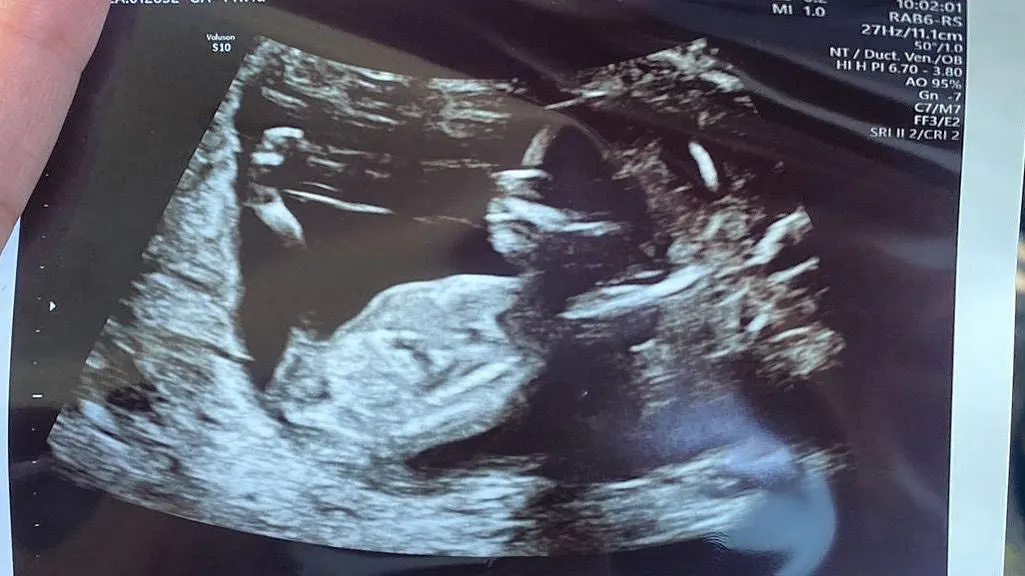

In juni liet Gijs weten voor het eerst opa te worden met een foto van de echo. "Zo bijzonder", schrijft hij, "#eerste #kleinkind #ever".